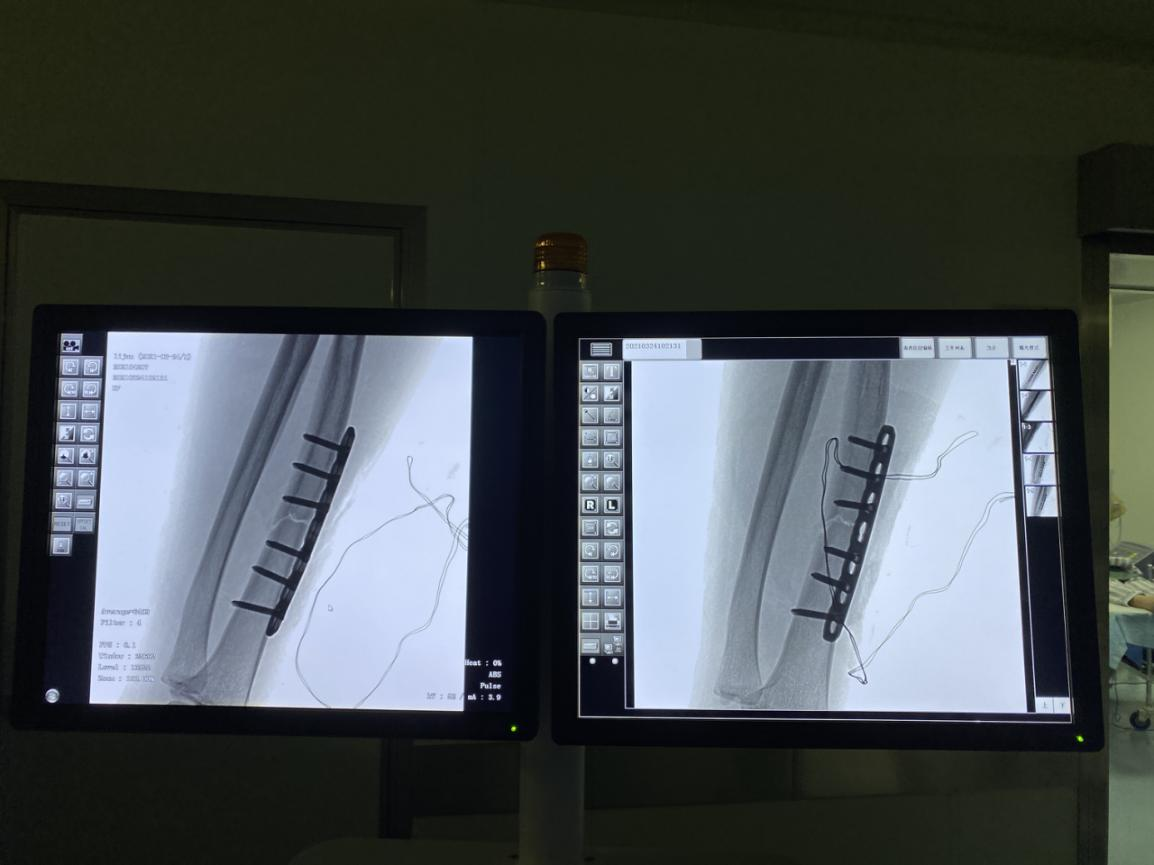

与孙先生详细沟通后,建议行手术切开复位并固定,孙先生表示认同,并入住我院准备手术。

术后孙先生手腕疼痛感明显减轻,肿胀等症状消失。